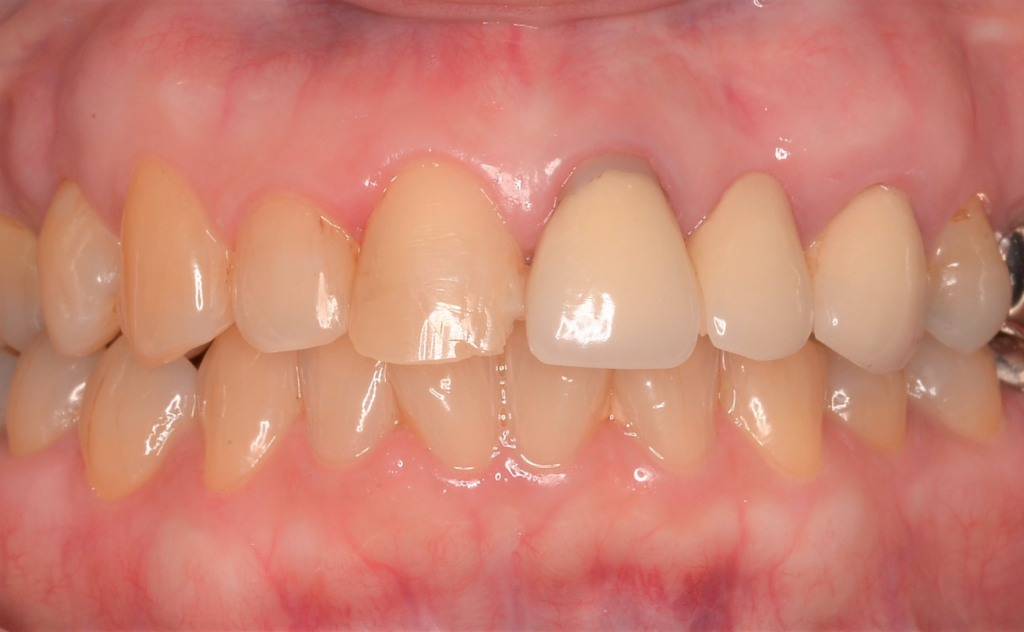

こんにちは✨しんデンタルクリニックです🌸 今回は、歯を失って奥歯で噛めないというお悩みをお持ちだった患者様のご紹介です&…more